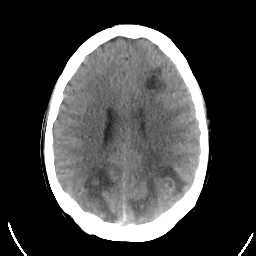

Sarcoma: Roentgen-ray CT -- Slice #16

[Home][Help][Clinical] Slice 16